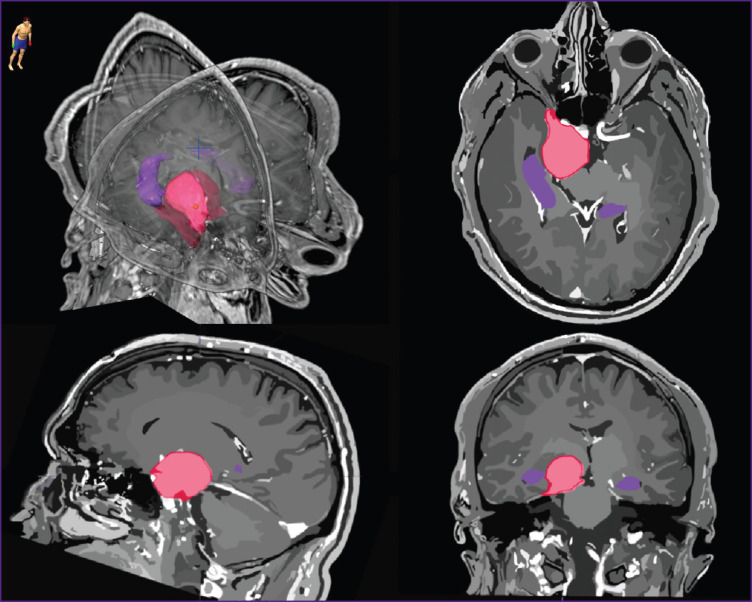

Materials and methods: A homogeneous sample of 28 patients with parasellar meningiomas adjacent to the hippocampus has been studied. In 16 patients, the tumor was diagnosed on the left side, in 12 patients on the right side. These two groups were comparable in terms of tumor morphometric characteristics and the degree of hemispheric compression. The control group consisted of 31 healthy subjects. All three groups were comparable in age and gender. The "Virtually Implanted Electrode" method was used to describe changes in brain network connectivity. The method allows for the reconstruction of electrical activity in any brain voxel based on its coordinates relative to scalp electrodes. To describe the functional connectivity of the brain, correlation coefficients between all pairs of the selected areas of interest were sequentially calculated.

Abstract Image